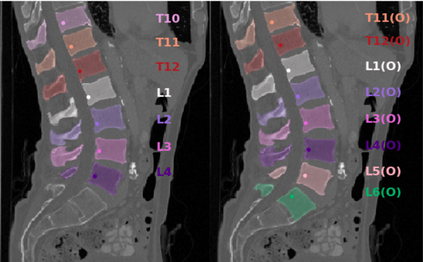

Vertebrae localization, segmentation and identification in CT images is key to numerous clinical applications. While deep learning strategies have brought to this field significant improvements over recent years, transitional and pathological vertebrae are still plaguing most existing approaches as a consequence of their poor representation in training datasets. Alternatively, proposed non-learning based methods take benefit of prior knowledge to handle such particular cases. In this work we propose to combine both strategies. To this purpose we introduce an iterative cycle in which individual vertebrae are recursively localized, segmented and identified using deep-networks, while anatomic consistency is enforced using statistical priors. In this strategy, the transitional vertebrae identification is handled by encoding their configurations in a graphical model that aggregates local deep-network predictions into an anatomically consistent final result. Our approach achieves state-of-the-art results on the VerSe20 challenge benchmark, and outperforms all methods on transitional vertebrae as well as the generalization to the VerSe19 challenge benchmark. Furthermore, our method can detect and report inconsistent spine regions that do not satisfy the anatomic consistency priors. Our code and model are openly available for research purposes.